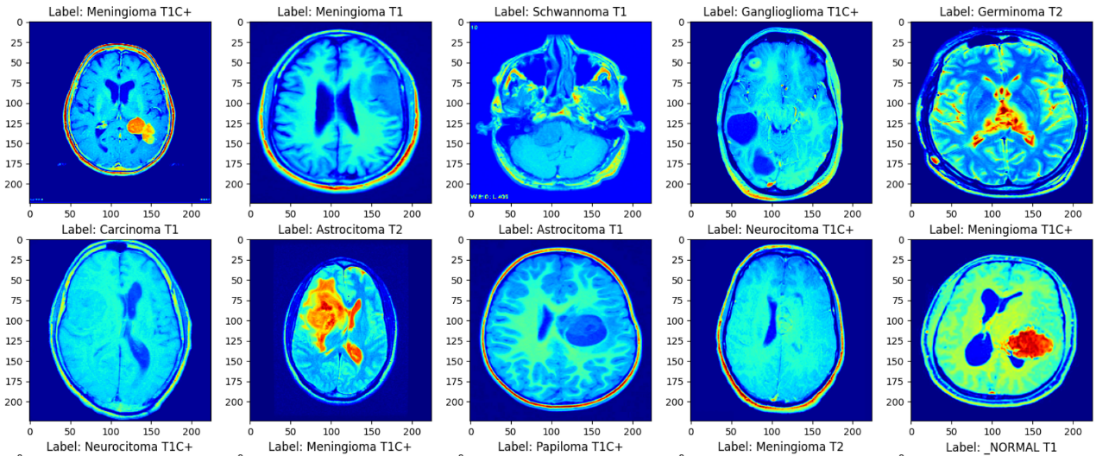

This study used a dataset of 44 Classes of Brain Tumor magnetic resonance imaging (MRI) Images in Kaggle [8]. A private collection of T1, contrast-enhanced T1, and T2 magnetic resonance images separated by brain tumor type. A total of 14 cancer images were clearly classified by radiologists. In terms of data processing, this study creates a data enhancement layer before data is input into the model. By way of mirror inversion and adjustment of sharpness. Thus, the number of data sets can be effectively expanded. Then, the data of different diseases in the data set were divided into the training set and the test set according to the ratio of 8:2. The sample is shown in the Figure 1.

/word/media/image1.png

Figure 1. The samples of the MRI images.